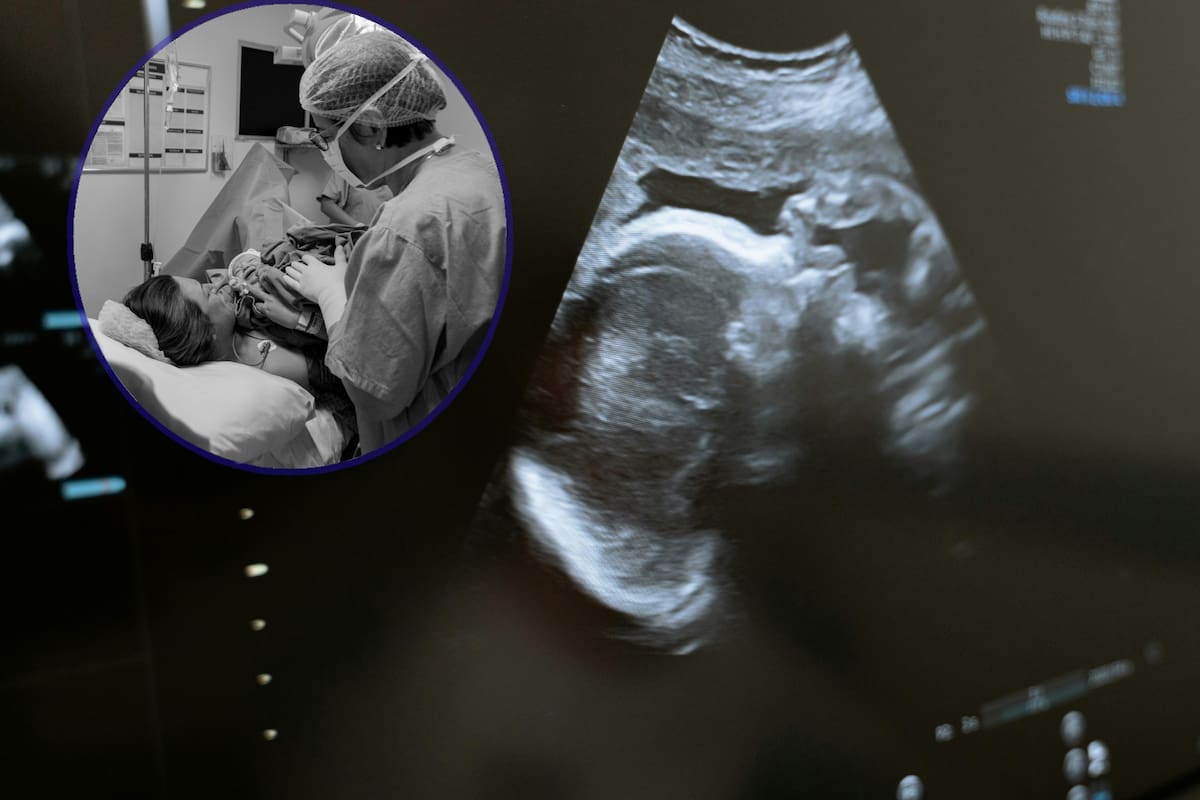

Médicos piden despenalizar el aborto en Puebla y frenar aumento de muertes

Un grupo de médicos de Puebla, con el apoyo de otros provenientes de diferentes estados del país, pidieron la despenalización del aborto en ese estado.

Este llamado que hacen estos profesionales de la salud, forma parte de la campaña “Salvemos Miles de Vidas México”. La especialista en ginecobstetricia Georgina Díaz, destacó que la mujer que decide abortar lo hará en las condiciones que puede, aun siendo ilegal. “Hemos vivido de cerca las consecuencias del aborto inseguro: hemorragias, infecciones, lesiones de útero, infertilidad e incluso la muerte. El aborto existió, existe y existirá”.

Aurora Morales Domínguez, ginecobstetra del estado de Puebla recordó que solo en el 2021, Puebla fue la octava entidad con mayor incidencia de abortos en el país y, “en promedio a nivel estatal, anualmente 4 mujeres mueren por abortos inseguros”.

De acuerdo a la Secretaria de Salud Federal, entre 2022 y 2023 el aborto aumentó como muerte de causa materna, pasando del 7.1% al 8.3%.

En 2022, el aborto inseguro fue la tercera causa de muerte materna en México. Verenice Gómez Vera, ginecobstetra de Puebla recordó que en el 2021 la Suprema Corte de Justicia de la Nación declaró que es inconstitucional establecer sanciones penales en aquellas féminas busquen interrumpir su embarazo en las primeras 12 semanas de gestación en México.

“Cuando el aborto es legal, es más sencillo acceder a un procedimiento seguro porque el personal de salud tiene la posibilidad de brindar atención y además cuenta con los insumos, los recursos y las tecnologías adecuadas. El aborto es altamente seguro pero, cuando está penalizado, nos quedamos de manos atadas y esto perpetúa las prácticas inseguras que incurren en procedimientos riesgosos o que se realizan sin información adecuada. Lo que queremos es salvar miles de vidas en México con abortos seguros”, concluyó la médica ginecobstetra del Estado de México, María Eréndira Itami Sordo.